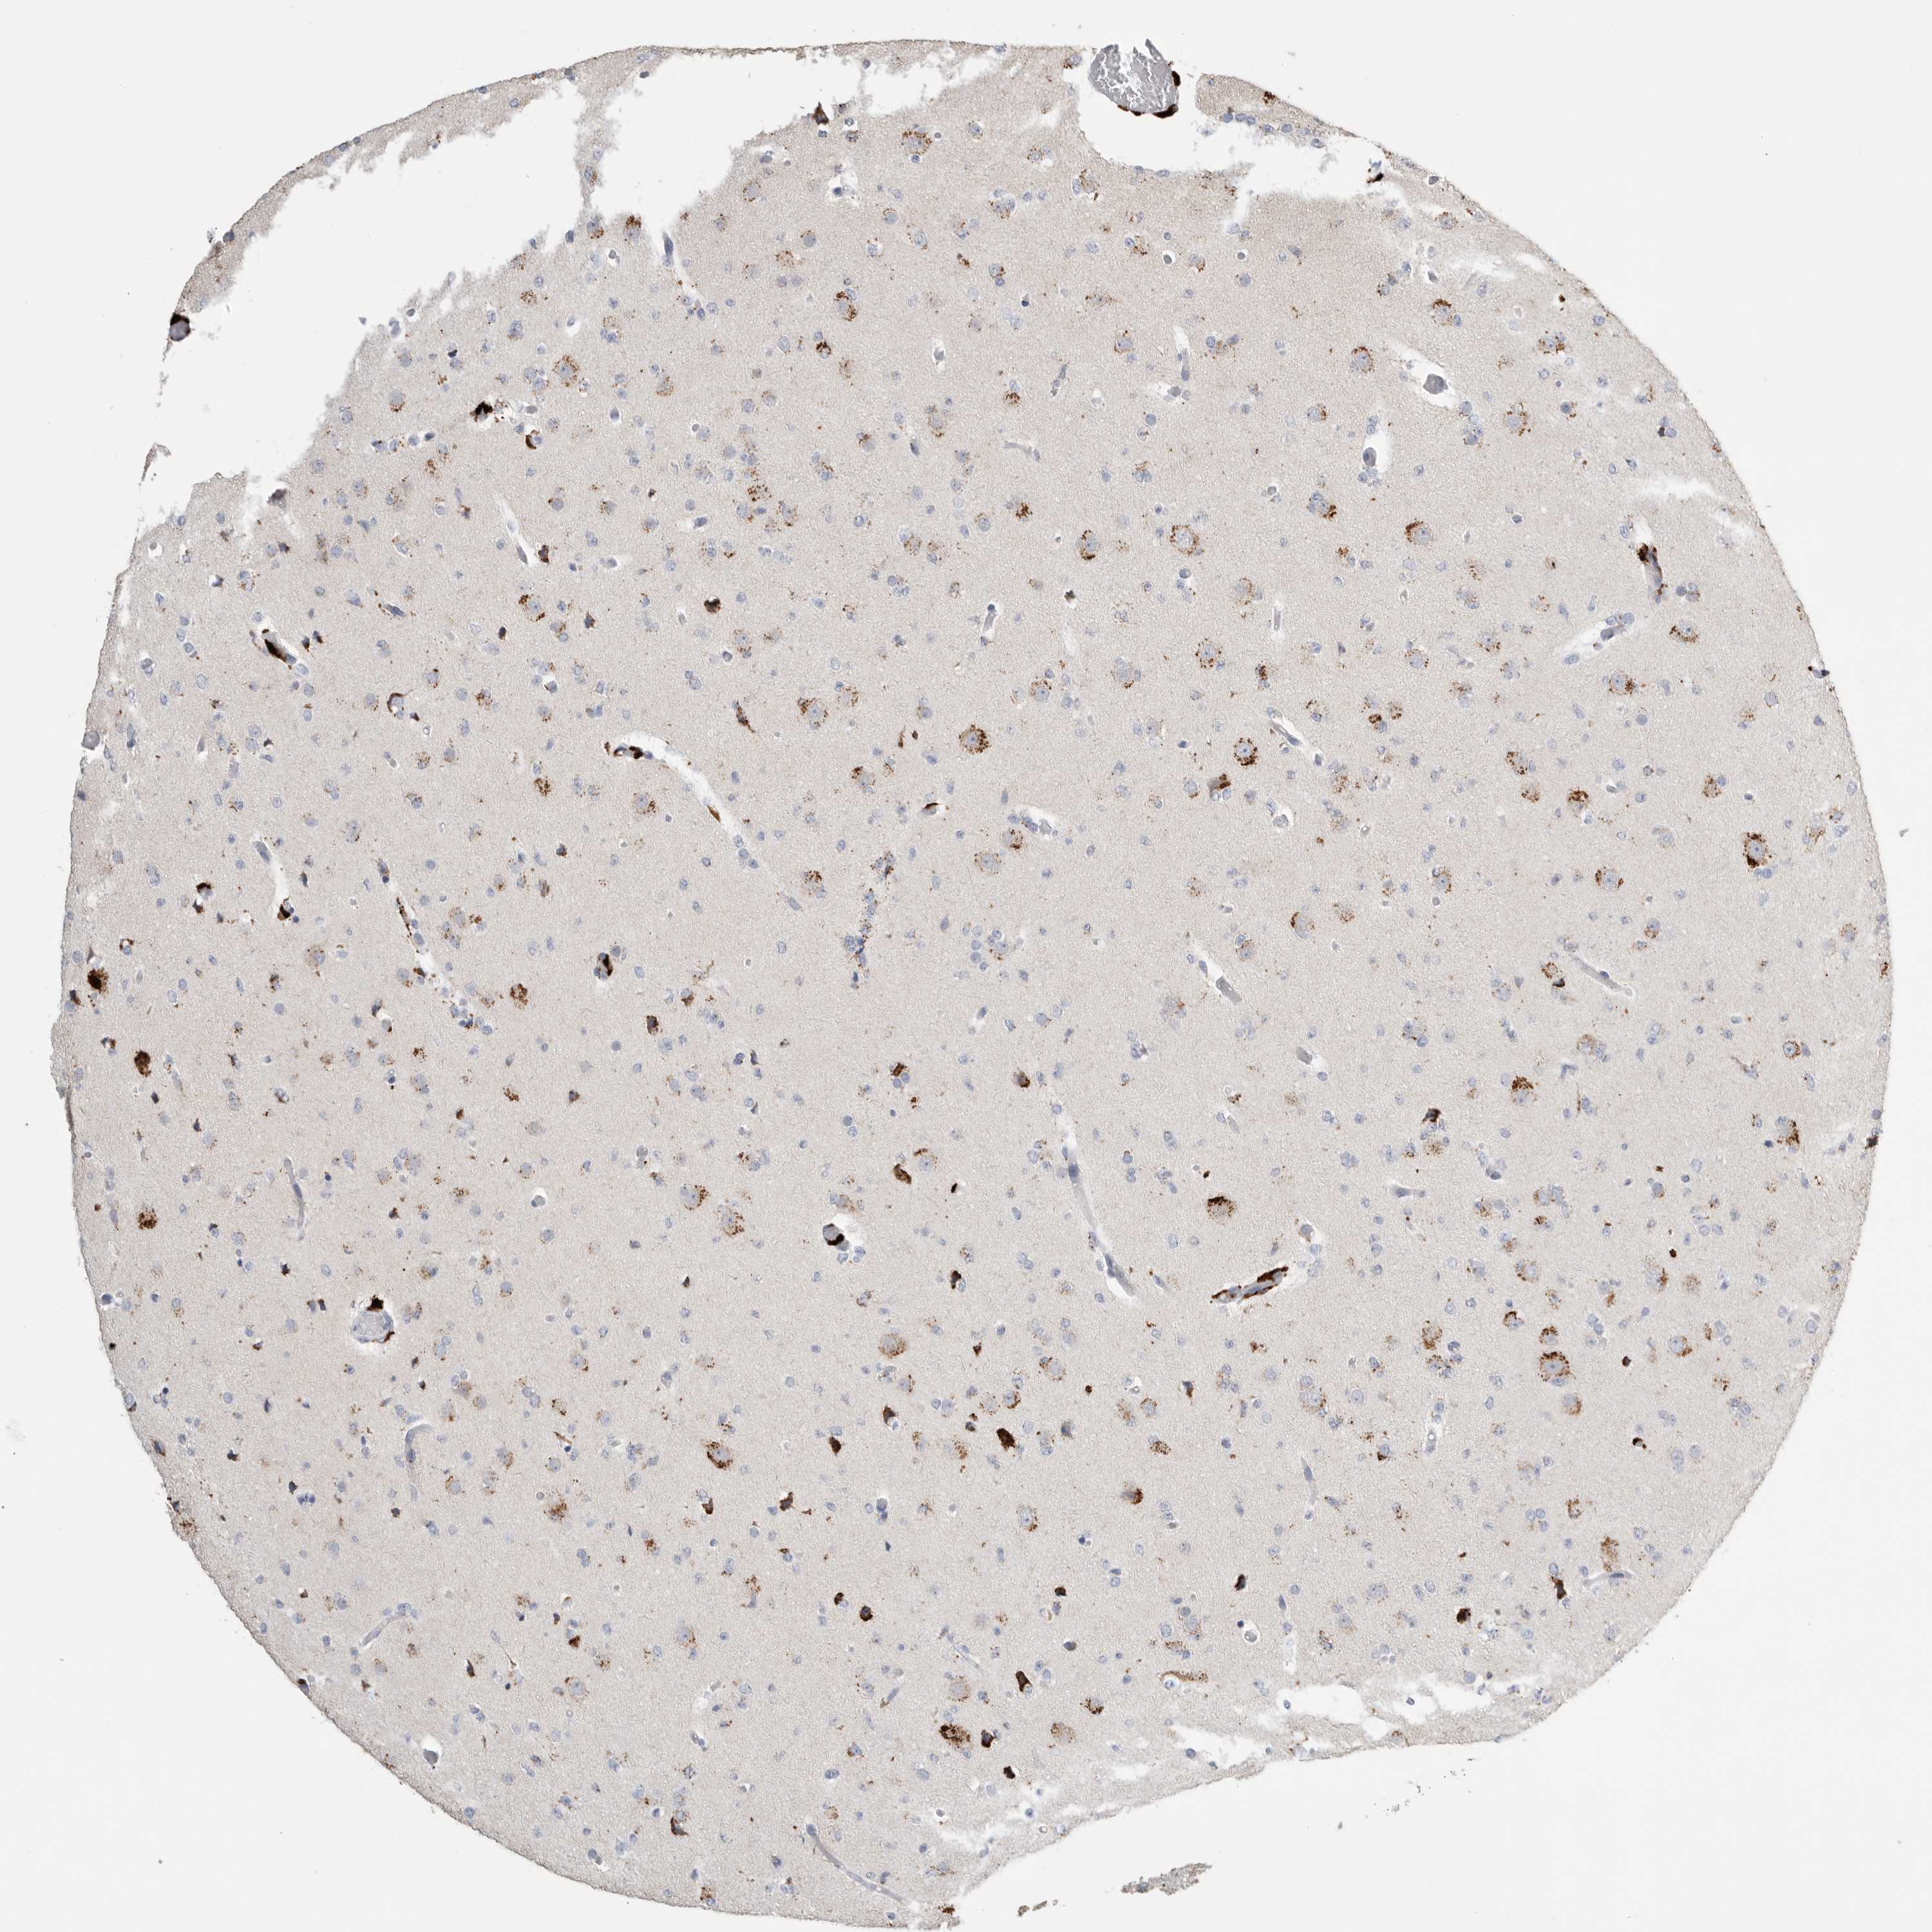

GLIOMA - Protein expressioni

A mouse-over function shows sample information and annotation data. Click on an image to view it in a full screen mode. Samples can be filtered based on level of antibody staining by selecting one or several of the following categories: high, medium, low and not detected. The assay and annotation is described here.

Note that samples used for immunohistochemistry by the Human Protein Atlas do not correspond to samples in the TCGA dataset.

Antibody stainingi

Antibody staining in the annotated cell types in the current human tissue is reported as not detected, low, medium, or high, based on conventional immunohistochemistry profiling in selected tissues. This score is based on the combination of the staining intensity and fraction of stained cells.

Each image is clickable and will lead to virtual microscopy that enables deeper exploration of all samples and also displays staining intensity scores, fraction scores and subcellular localization as well as patient and tissue information for each sample.

Antibody HPA025226

Antibody CAB019296

Glioma, malignant, High grade

Glioma, malignant, Low grade